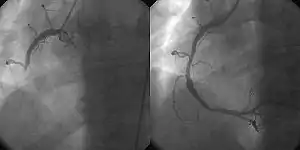

- Percutaneous coronary intervention (PCI/Coronary angioplasty)

- the use of angioplasty for the treatment of obstruction of coronary arteries as a result of coronary artery disease. A deflated balloon catheter is advanced into the obstructed artery and inflated to relieve the narrowing; certain devices such as coronary stents can be deployed to keep the blood vessel open. Various other procedures can also be performed at the same time. After a heart attack, it can be restricted to the culprit vessel (the one whose obstruction or thrombosis is suspected of causing the event) or complete revascularization; complete revascularization is more efficacious in terms of major adverse cardiac events and all-cause mortality.[4]